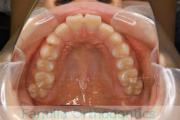

上の出っ歯、口が閉じにくい、下の前歯のガタガタを治したいということで来院されました。上顎から左右小臼歯を、下の前歯は凹凸が非常に強いので、こちらから一本抜歯を行いました。2年強、30回程度の通院が必要でした。

成人になってからの叢生(でこぼこ、凹凸、ガタガタ)は、保定をしっかりしないと後戻りをしてしまうリスクが高いです。

上顎

下顎